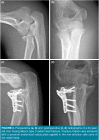

Patients and methods: Between January 2012 and December 2019, a total of 27 patients (16 males, 11 females; median age: 43.2 years; range, 20 to 68 years) with Mason type 3 radial head fractures were retrospectively analyzed. The patients were divided into two groups according to fixation method used. Group 1 consisted of 12 patients who were treated with tripod technique, and Group 2 consisted of 15 patients who were treated with locked plate fixation. Operation time, follow-up period, length of hospital stay, union time, Disabilities of Arm, Shoulder and Hand (DASH) scores, range of motions and complications were recorded.

Conclusion: Our study results demonstrate that comparable results can be achieved in both techniques regarding functional outcome and range of motion. With a shorter union time and less complication rates, the tripod technique should be considered as the primary treatment method for the comminuted radial head fractures without a metaphyseal defect.